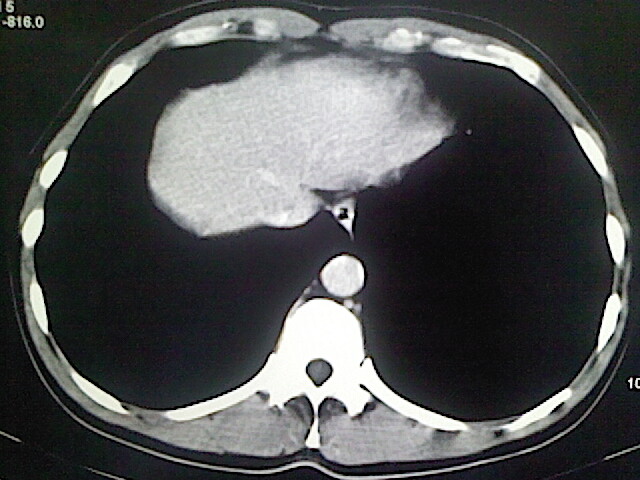

以下是引用卜一在2009-3-14 9:49:00的发言:[br]胆囊萎缩,胆囊壁不规则增厚,内部结构模糊,增强明显强化。另:肝左叶外侧段肝囊肿。支持:慢性胆囊炎!高度可疑:胆囊癌!

以下是引用余辉在2009-3-14 8:48:00的发言:[br]1)慢性胆囊炎。2)肝左叶外侧段肝囊肿。3)脂肪肝。[br]支持,胆囊萎缩,密度增高,不知b超具体有何提示,钙胆汁?结石?

以下是引用jiangjing在2009-3-14 10:18:00的发言:[br]1)慢性胆囊炎。2)肝左叶外侧段肝囊肿。3)脂肪肝。4.】建议行肝功能检查